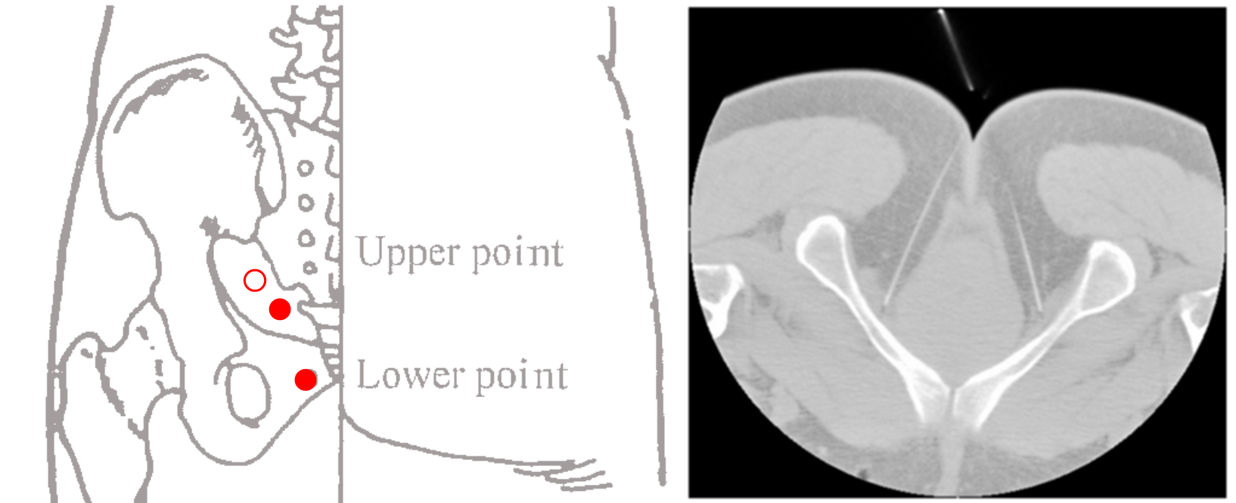

- Rééducation périnéale standardisée + acupuncture (figure 1, 2 et 3)

- Rééducation périnéale standardisée + fausse acupuncture acupuncture (figure 1 et 3)

Figure 1. Protocole d'acupuncture (d'après Niu J et al., 2025)

Le protocole d'acupuncture

L’étude utilise la technique de puncture profonde intraforaminale des baliao (ici limités au 32V, 33V et 34V), telle que décrite par la Pr Wang Linling [3]. Les auteurs appartiennent d’ailleurs, comme elle, à l’Université de médecine chinoise de Nanjing. Par rapport à la technique initialement décrite, une variante apparaît : l’angle de puncture, outre son inclinaison par rapport à la peau, est également modifié selon les points par rapport à la ligne médiane (figure 3). Bien que cette technique ait déjà fait l’objet de nombreuses études cliniques en urologie, il s’agit ici de la première étude contrôlée randomisée consacrée à l’incontinence urinaire après prostatectomie.

Les deux points supérieurs sont situés 1 cm latéralement à la jonction sacro-coccygienne et les deux points inférieurs 1 cm latéralement à la pointe du coccyx, ce qui correspond en pratique au 35V (figures 6 et 7).

La technique utilise des aiguilles longues et relativement rigides (0.40 x 100 mm ou 0.40 x 125 mm). Au point supérieur, l'aiguille est insérée perpendiculairement sur une profondeur d’environ 80 à 90 mm, et au point inférieur obliquement vers la fosse ischio-rectale (figure 7) sur 90 à 110 mm. La puncture doit déclencher un deqi avec irradiation à l'urètre ou contraction de l'anus.